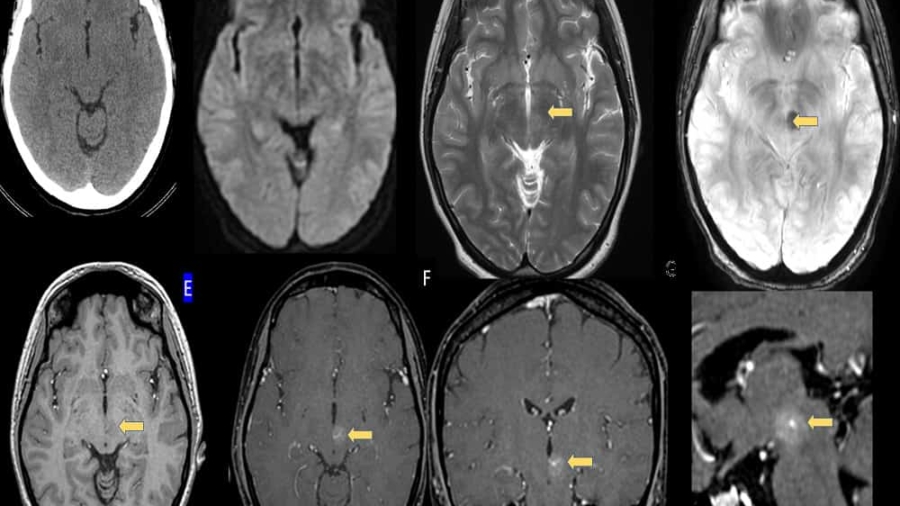

A 21 year old male was brought for evaluation of fever since 45 days associated with holocranial headache for 30 days and altered sensorium for 20 days . Working clinical diagnosis of chronic meningoencephalitis was made for which cross sectional imaging was requested.